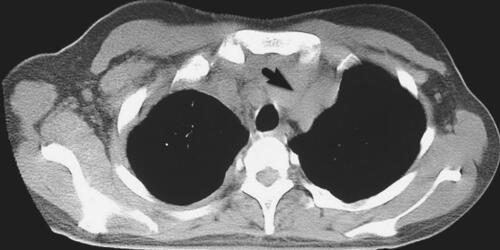

入院体检:生命体征平稳,全身浅表淋巴结无肿大,气管居中,右胸语音震颤减弱、右侧中下肺叩诊实音、听诊呼吸音减弱。心界无扩大、肝脾肋缘下未触及、移动性浊音阴性、双下肢无水肿。初步诊断“右侧胸腔积液性质待查 结核性胸膜炎?”。入院当天即行胸腔积液穿刺,抽出淡黄色胸腔积液600ml,胸腔积液常规示:李凡他试验阳性,比重1.030,有核细胞2250×106/L,单个核细胞95%,多个核细胞5%,间皮细胞可见;胸腔积液生化:葡萄糖4.59mmol/L、蛋白48g/L、乳酸脱氢酶(LDH)2184U/L;胸腔积液腺苷脱氨酶(ADA)122U/L;胸腔积液浓缩找抗酸杆菌阴性;胸腔积液CEA 0.99ng/ml;胸腔积液细胞学:大量淋巴细胞,异型淋巴细胞较多见,可见少量中性粒细胞,未发现肿瘤细胞;红细胞沉降率58mm/h。综上考虑结核性胸膜炎可能性大。治疗上,继续抽取胸腔积液、并于9月2日试行进行四联抗结核治疗:异烟肼300mg,1次/日,利福平450mg,1次/日,乙胺丁醇750mg,1次/日,吡嗪酰胺250mg,3次/日。患者体温无下降,胸腔积液经多次穿刺后仍生长迅速。2011年9月5日、7日患者复查胸腔积液LDH分别为2263U/L、2259U/L;胸腔积液ADA分别为125U/L、133U/L。9月9日第3次胸腔积液细胞学结果显示:“大量淋巴细胞,可见少量异常核淋巴细胞,考虑为恶性细胞,建议除外淋巴瘤”。9月9日行胸部CT(图1)示:上纵隔占位病变。经前纵隔肿物活检形态学及免疫组化考虑为硬化性大细胞性淋巴瘤,B细胞型,免疫组化CD20(+),CD79a(部分+),Ki-67(50%+),MUM-1(+)。综上,诊断为:纵隔原发性大B细胞淋巴瘤(弥漫大B细胞性非霍奇金淋巴瘤)。

图1 纵隔原发性大B细胞淋巴瘤并发胸腔积液